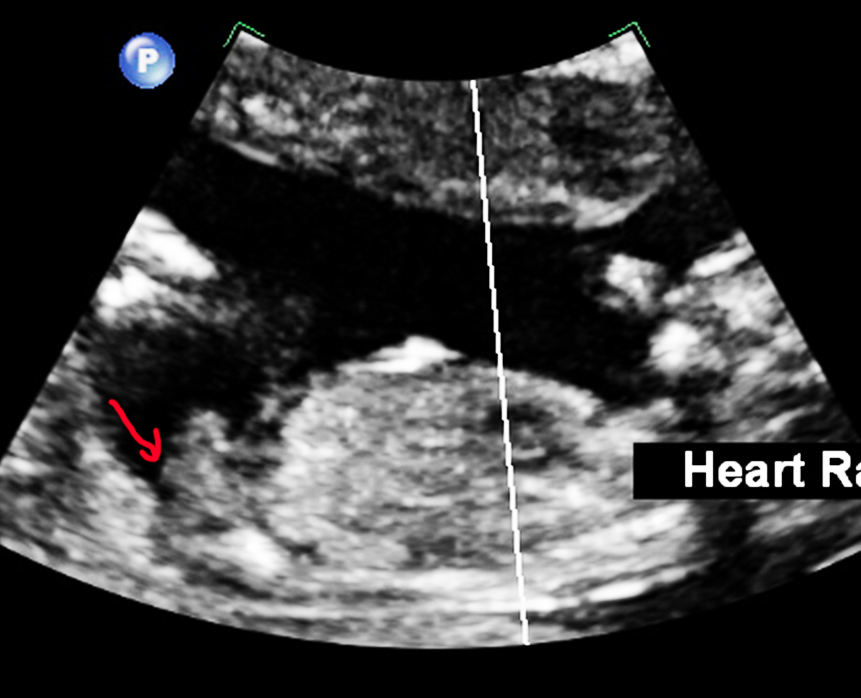

youve got a lot of cord going on but id give it a boy lean

It's a tricky one. I had a nub just like that (confirmed girl) in one of my shots and it looks boy at first but because of how the baby is almost sitting upright it's just a weird angle so I'm guessing girl

Leaning girl

I think the nub is a bit higher. Careful boy lean. Lots going on doen there